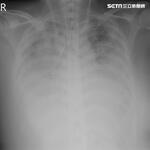

刺突蛋白 & 奈米脂質顆粒(

LNP

, Lipid nanoarticles)造成持續傷害 &

自體免疫紊亂

的機制終於投入大量資金製作成動畫,有中文字幕。

所有廠牌的實驗針劑都不安全,包括高端,且不限於流感疫苗。